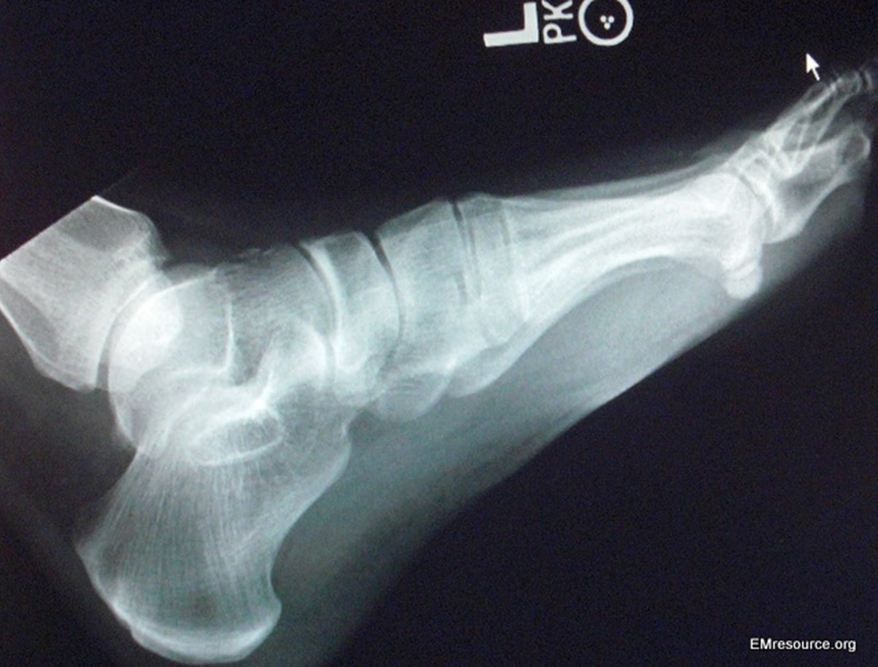

Figure. Lateral view, foot x-ray. Click to enlarge.

A 32-year-old man presents to the emergency department with a foot injury that occurred when he landed on a rock after jumping down from a 7-foot wall onto uneven ground. He denies other injury and points to the forefoot and lateral malleolus as the areas of most severe pain. He is unable to walk.

On physical exam, the skin is intact and there is mild foot swelling, but no deformity, bruising or tense compartments. There is tenderness to entire proximal foot and to the lateral malleolus so plain film x-rays are ordered. The AP and mortise views are normal. The lateral view is shown in the Figure, left.

What fracture is shown? Make sure to click on image to enlarge and view magnified version; look carefully.